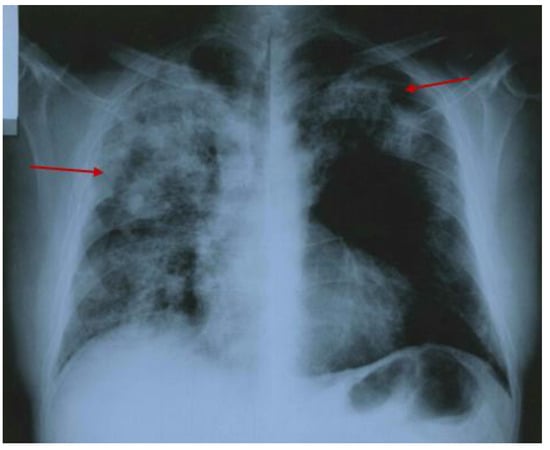

3.2.2. Additional Imaging Assessments

| Kim 2018 [52] | 58 M | Ascending aorta: eccentric thickening of the aortic wall Mid-sternal pain, fever, and cough | Pulmonary infiltrates Hilar lymphadenopathy Scleral keratitis Pituitary adenoma resection | cANCA positive | PT: GC | Dimensional reduction in peri-aortic mass and pulmonary nodule |